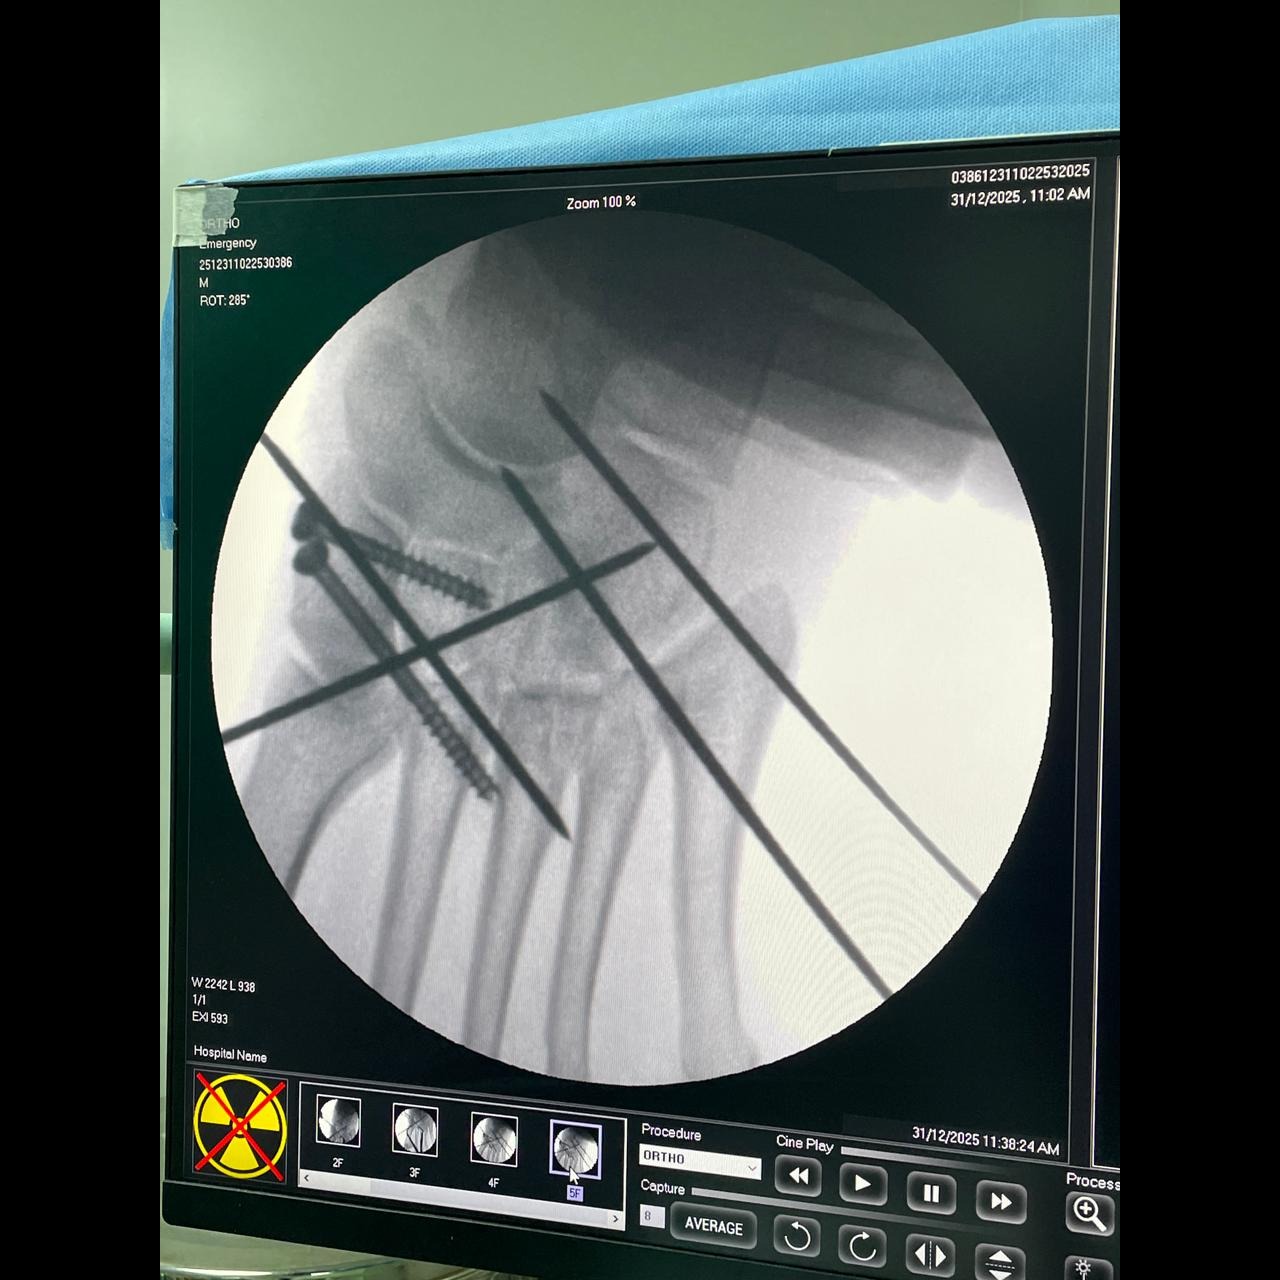

Lisfranc dislocation reduced completely !